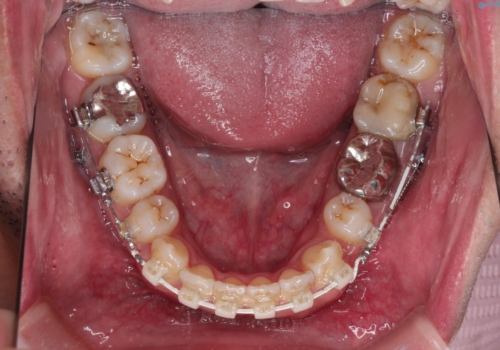

- 審美装置(ブラケット:白/ワイヤー:白)

- 2年3ヶ月

- 10-30回